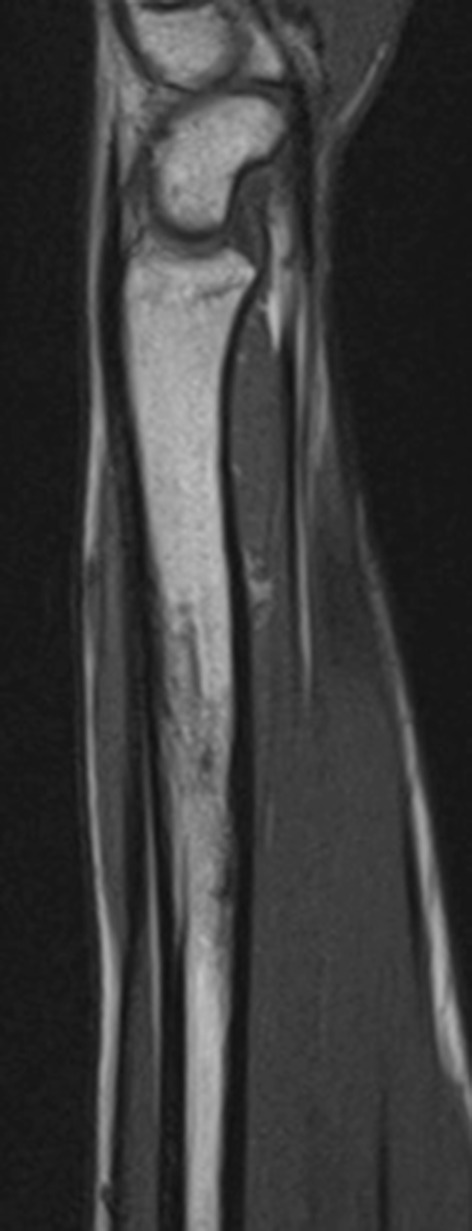

Fig. 3.

MRI scan of the left distal radius showing cystic lesions in the distal radius with surrounding oedema and an area of cortical discontinuity